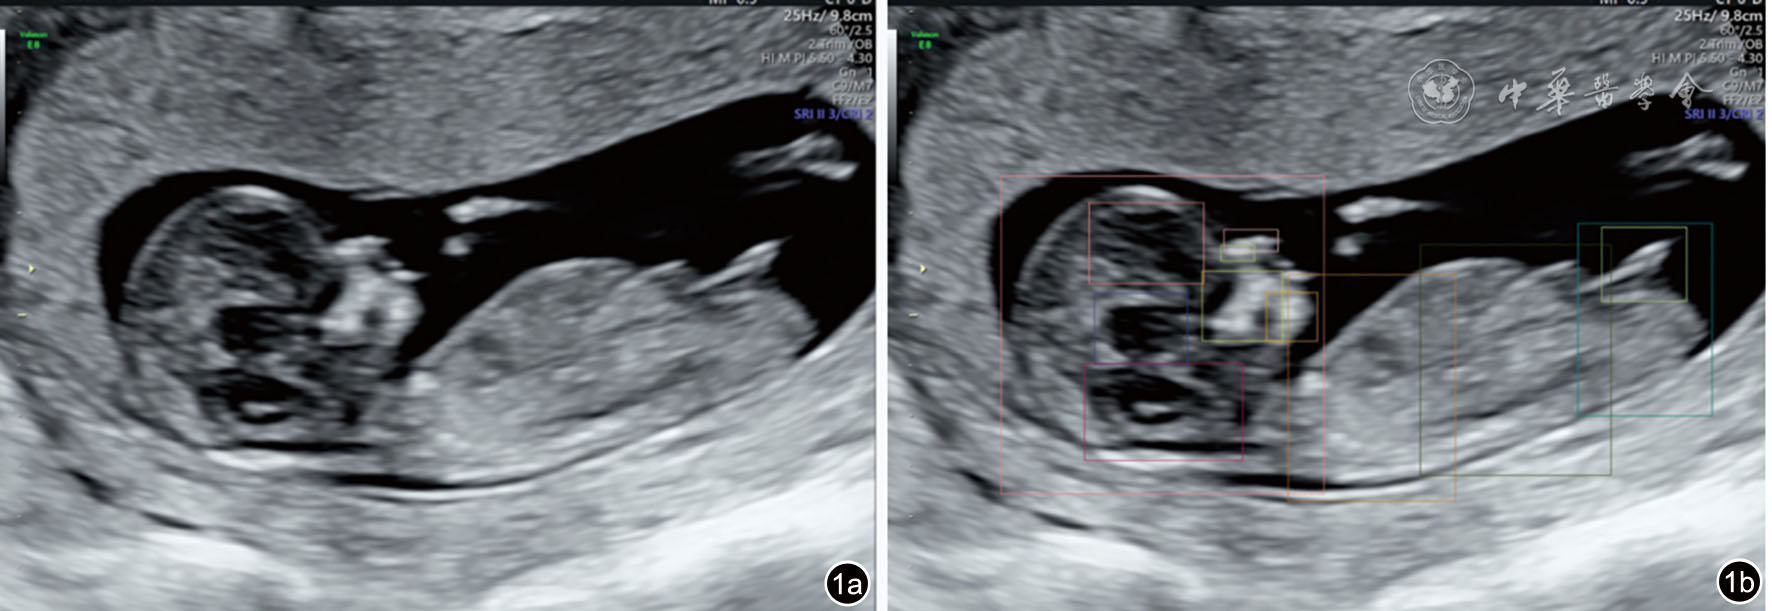

图1 产前超声人工智能智慧云平台对胎儿头臀长切面质量控制超声图像。质量控制结果包括检测结构显示情况(鼻骨、鼻尖和鼻前皮肤、上颌骨、下颌骨、间脑、菱脑、生殖器、侧脑室、头、胸、腹、臀)和总体评价,总体评价包括切面名称、切面质量(标准)、切面评分(94分)、结构置信系数评价(鼻骨:0.53,鼻尖和鼻前皮肤:0.68,上颌骨:0.86,下颌骨:0.46,间脑:0.89,菱脑:0.83,生殖器:0.80,侧脑室:0.69,头:0.89,胸:0.80,腹:0.81,臀:0.78)及不足原因。图a为原图,图b为质量控制标注图 |